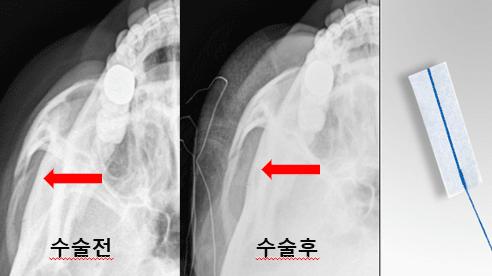

박 과장은 수술 전 단계에서부터 기존과는 다른 접근을 시도했다. 방사선에 식별 가능한 cottonoid(수술용 거즈)를 환자의 얼굴 표면 특정 위치에 부착한 뒤 X-ray 촬영을 시행해, 피부 표면 기준과 골 구조 간의 상대적 위치를 동시에 시각화한 것이다.

이 방법을 통해 단순 영상이 아닌, 실제 수술 중 조작해야 할 골절 부위의 방향성과 깊이감을 직관적으로 파악할 수 있었다. 이후 수술 중에도 동일한 기준점을 활용한 반복적인 X-ray 확인으로, 전후 및 상하 위치를 정밀하게 보정하며 환원을 진행했다.